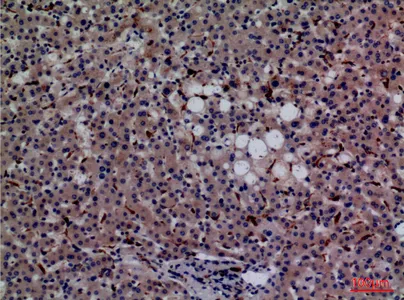

YAP (phospho Ser127) Rabbit Polyclonal Antibody

Cat: APRab05637

Size1:50μl Price1:$128

Size2:100μl Price2:$230

Size3:500μl Price3:$980